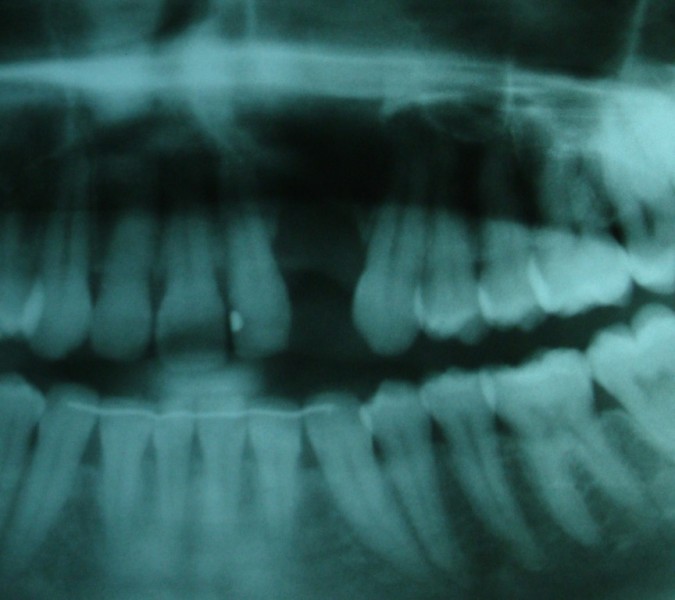

Sinus Lift